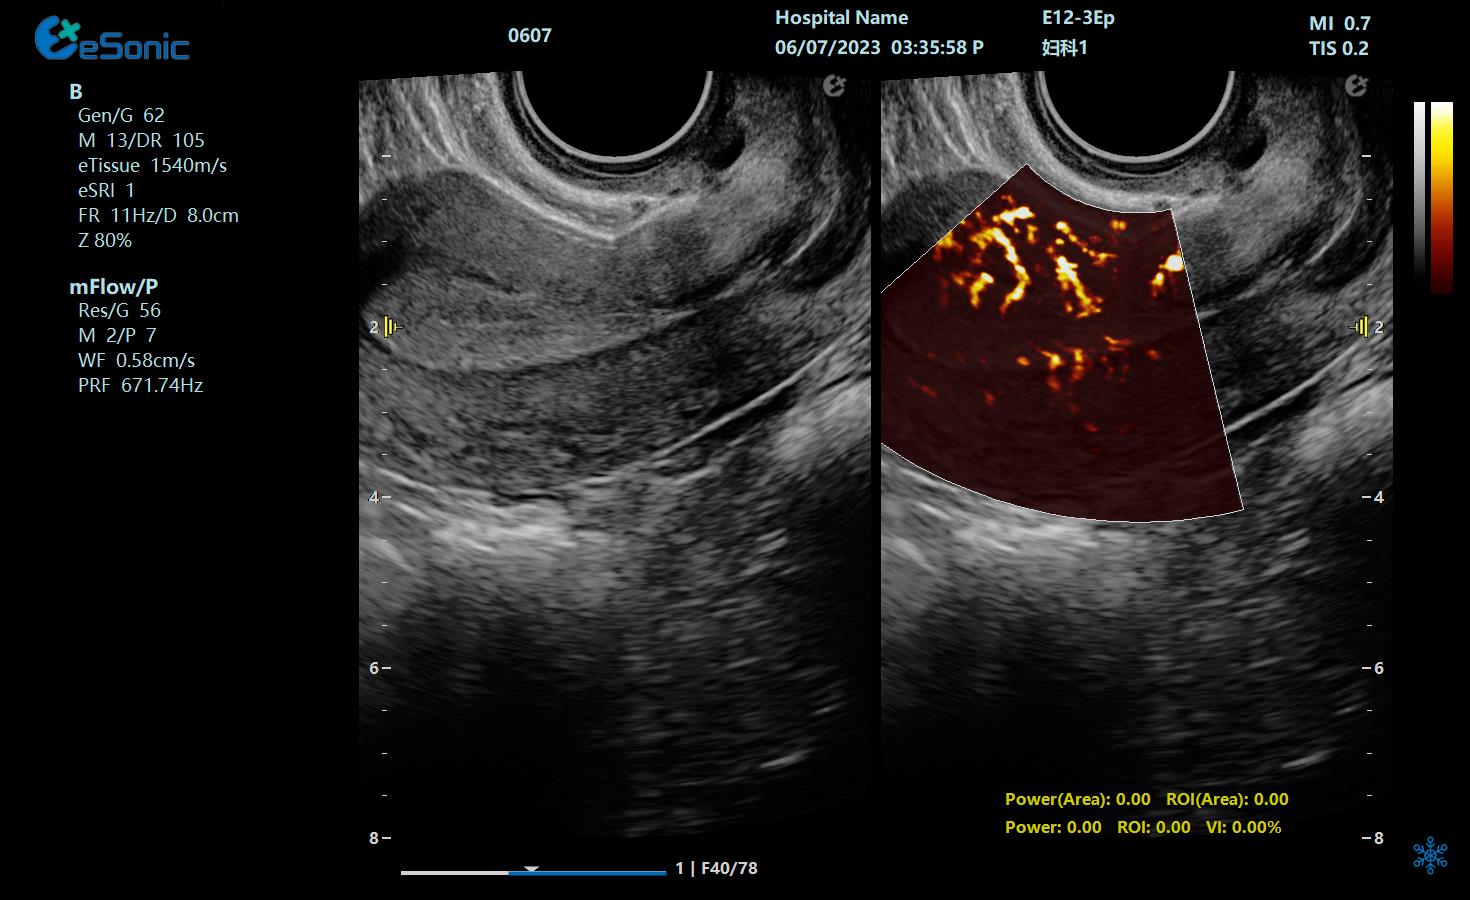

mFlow子宫内膜下螺旋动脉